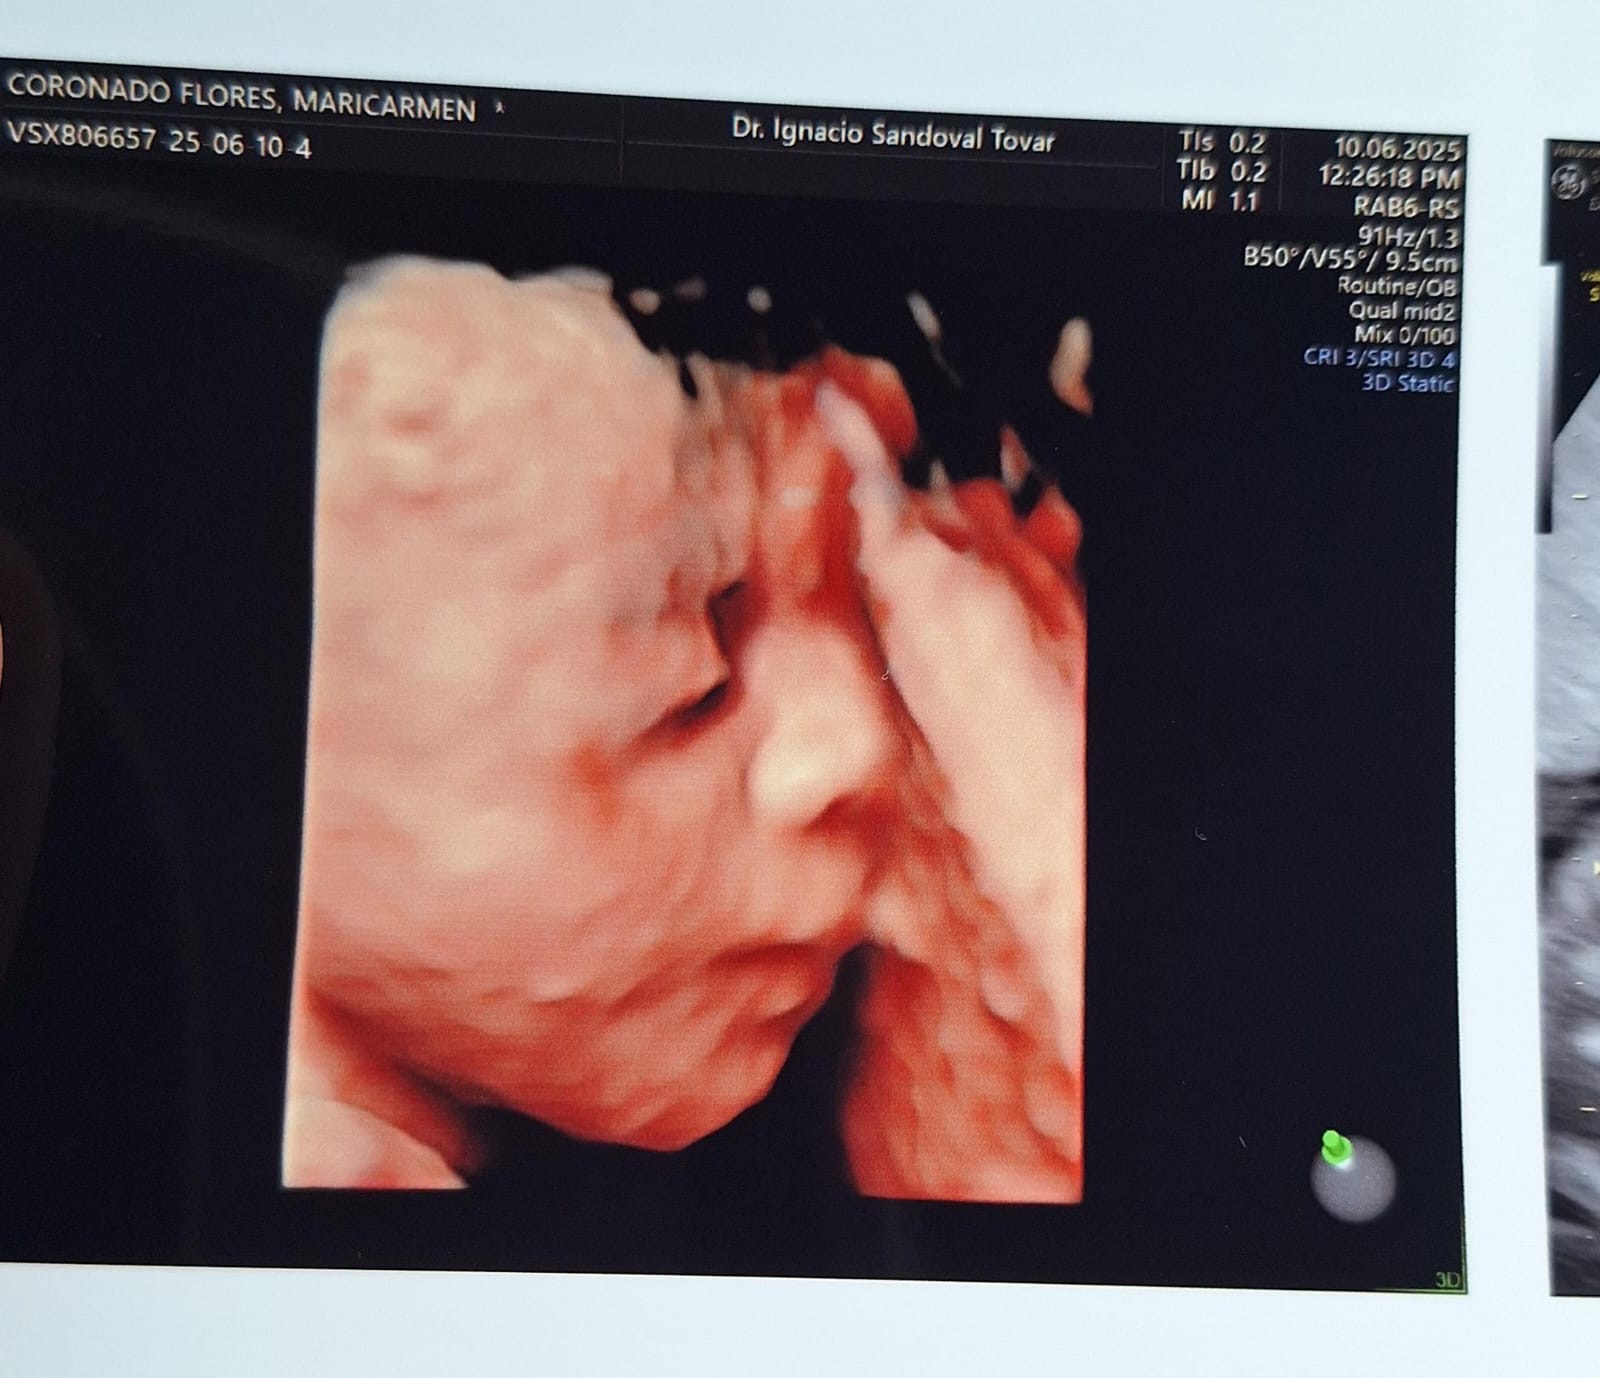

**En la madrugada del 10 de Julio se le rompió la fuente a Mari, nos fuimos de emergencia a Guadalajara Jalisco, donde será atendido nuestro bebe**

Hola mi nombre es Einar Nicolás y aún me encuentro en la pancita de mamá, hace poco me diagnosticaron una condición llamada Pentalogía de Cantrell lo que provoca que mi hígado, intestino y corazón se desarrollen fuera de mi cuerpo. Mamá y Papá descubrieron una clínica donde pueden atender esta condición y darme una oportunidad de vida, pero estas cirugías que necesito son muy costosas por eso están recaudando fondos. ¡Gracias por tu ayuda!

Hello, my name is Einar Nicolás and I'm still in mom's belly, I was recently diagnosed with a condition called Cantrell's Pentalogy which causes my liver, intestine and heart to develop outside my body. Mom and Dad discovered a clinic where they can take care of this condition and give me a chance at life, but these surgeries I need are very expensive that's why they're raising funds. Thank you for your help!